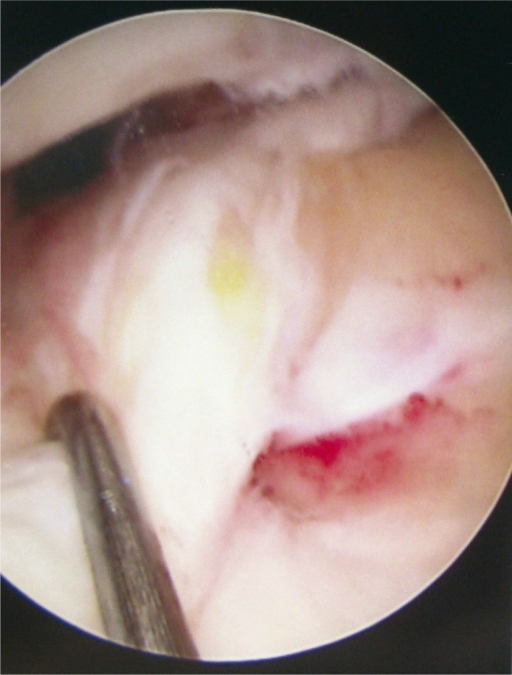

Examen del interior de una articulación realizado con un endoscopio especialmente diseñado que se introduce a través de una pequeña incisión. Este procedimiento, empleado fundamentalmente en problemas de rodilla, permite realizar una biopsia del cartílago o de la sinovial, así como diagnosticar una rotura de menisco o extraer cuerpos extraños del espacio articular.

Inspection of the interior of a joint (usually the knee) to diagnose any disorder here. The instrument used is a type of endoscope called an arthroscope.